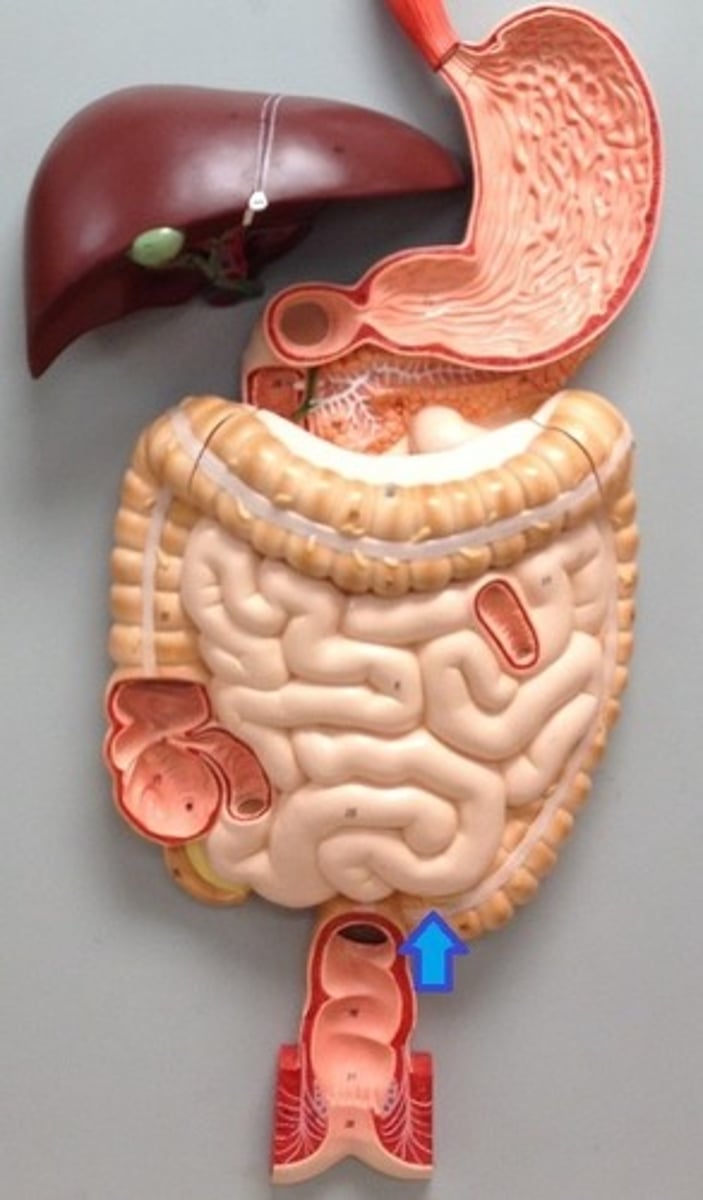

stomach

fundus

cardia

body

lesser curvature

greater curvature

cardiac sphincter / lower esophageal sphincter

pylorus

pyloric sphincter

rugae

lesser omentum

greater omentum

duodenum

duodenum

jejunum

ileum

large intestine

liver

Gallbladder

pancreas

spleen